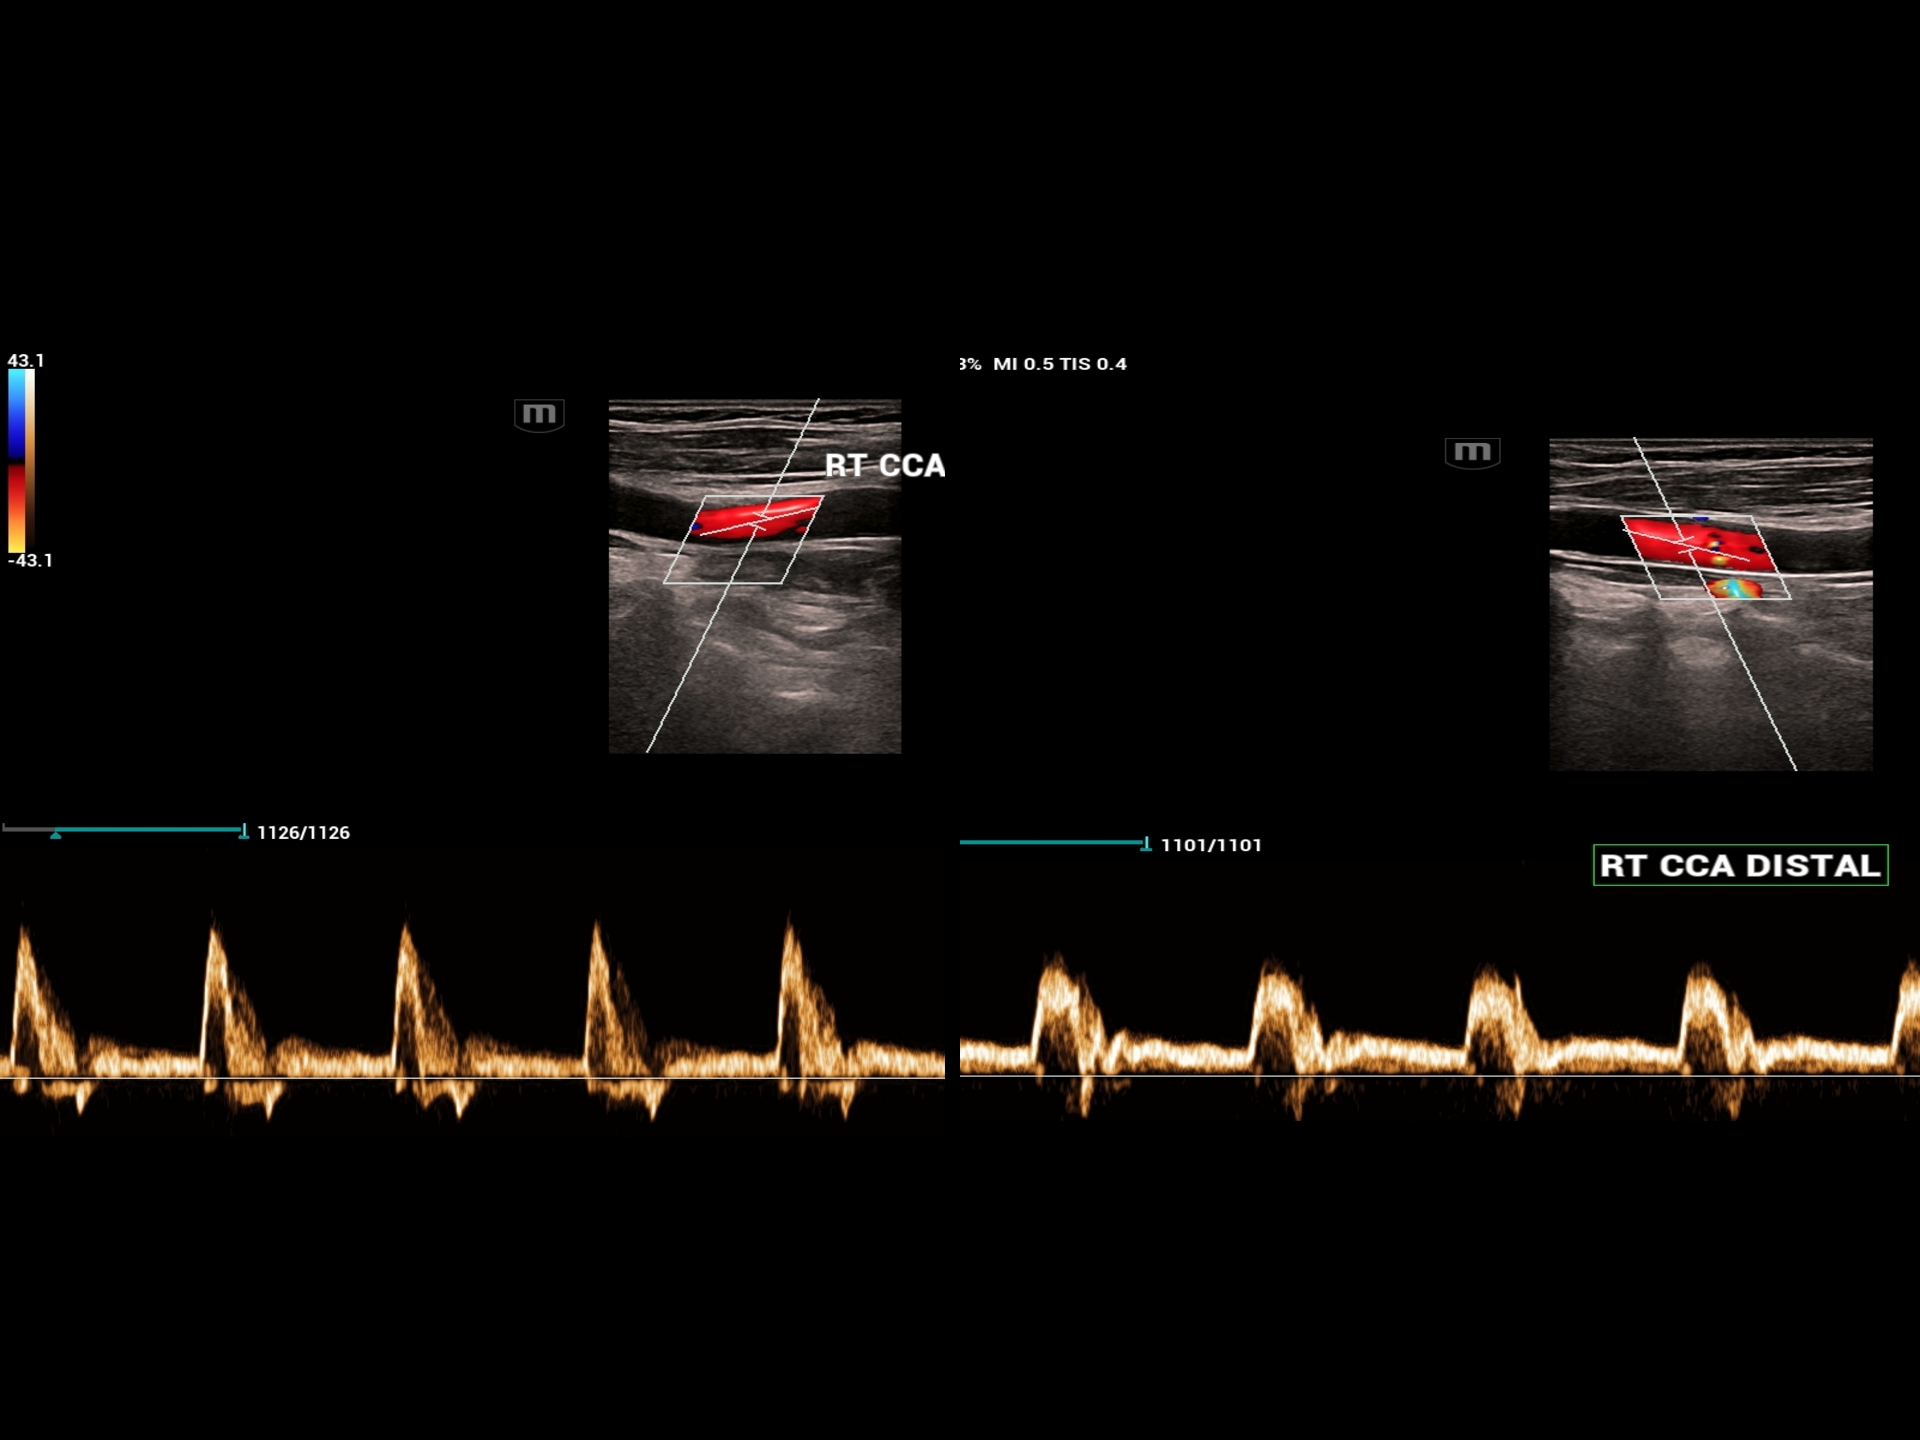

• Carotid Doppler to evaluate the atherosclerotic changes and risk evaluation for stroke.